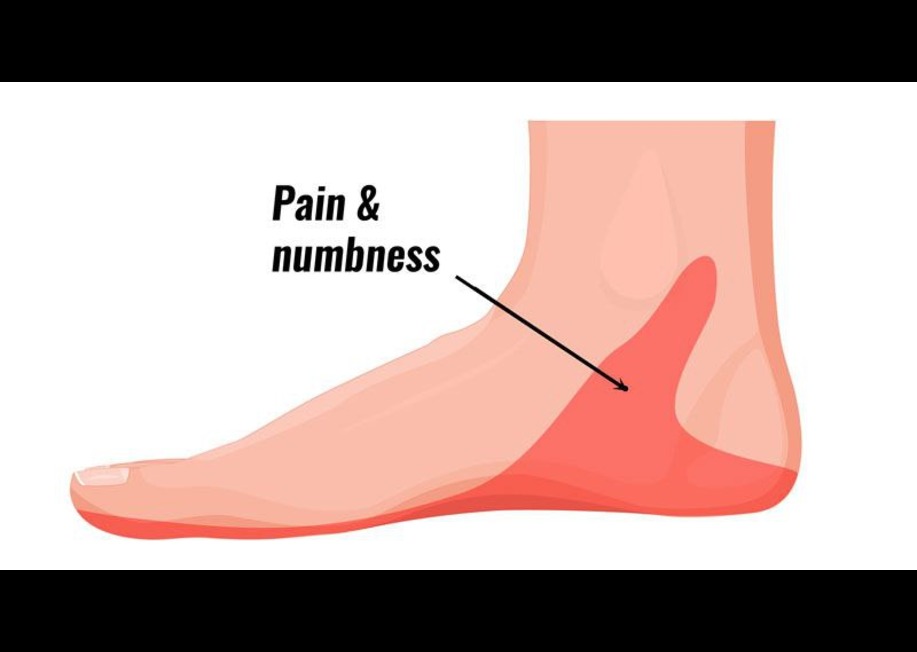

سندروم تونل تارسال زمانی به وجود میآید که علائم و نشانههای مختلفی در قسمت پا به وجود آمده باشد که ناشی از فشار بر عصبی به نام تیبیال در پشت قوزک داخلی مچ پا هستند. این سندروم در قوزک پا شباهت زیادی به سندروم تونل کارپال در قسمت مچ دست دارد.(تصویر شماره ۲)

سندرم تونل تارسال یک عارضهی دردناک است که کف پا را درگیر کرده و علت ایجاد آن، فشار بر روی عصب تیبیال خلفی است که از درون تونل تارسال میگذرد.

علائم سندروم تونل تارسال

علائم بسته به هر فرد متفاوت هستند. در حالی که برخی افراد علائم را به صورت تدریجی تجربه میکنند، برخی دیگر علائمی را تجربه می کنند که به صورت بسیار ناگهانی پدیدار می شوند.

بیمار معمولا در کف پا و قسمت داخلی مچ احساس درد میکند همراه با:

- سوزن سوزن شدن

- درد تیز و تیر کشنده

- احساس سوزش و گز گز در کف پا

- بی حسی

- احساس برق گرفتگی

- ضعف در عضلات خم و راست کننده انگشتان پا

- تورم اطراف قوزک و از مچ به پایین

- و احساس گرمی یا سردی در بالا و پایین پا.